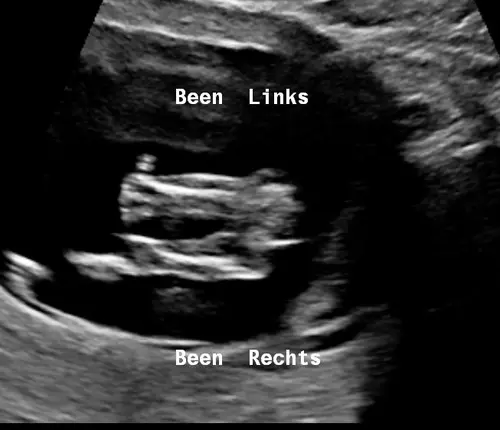

Klopt het dat dit een piemeltje is?

Nee volgens mij wordt hier het bovenbeen gemeten. Ik zie echt geen piemeltje op deze echo. 🫢😵💫

Nee volgens mij wordt hier het bovenbeen gemeten. Ik zie echt geen piemeltj ...

Oh haha ik dacht dat uitsteeksel er tussenin 🤭

Ik moest er nog eens naar kijken. Scherm gedraaid. Ik keek er anders tegen aan. 🫣🤣

Ja ik denk dat je hier idd een piemeltje ziet. 💙🤞